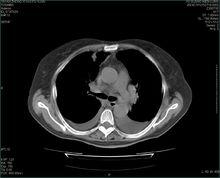

膀胱類型膀胱類型(types of urinary bladder):脊椎動物的膀胱可分為導管膀胱、泄殖腔膀胱和尿囊膀胱3種類型。圓口類、軟骨魚、部分爬行類及鳥類(鴕鳥例外)全無膀胱,其他脊椎動物皆有膀胱。

導管膀胱為輸尿管(中腎管)後端膨大形成,見於硬骨魚。泄殖腔膀胱由泄殖腔腹壁突出而成,故中腎管和膀胱不直接發生聯繫。

泄殖腔孔靠括約肌的收縮平時關閉著,尿液由泄殖腔倒流入膀胱內貯存。見於肺魚、兩棲類及哺乳類中的單孔類。

膀胱後視圖尿囊膀胱為胚胎時期尿囊柄的基部膨大而成。見於少數爬行類和哺乳類。